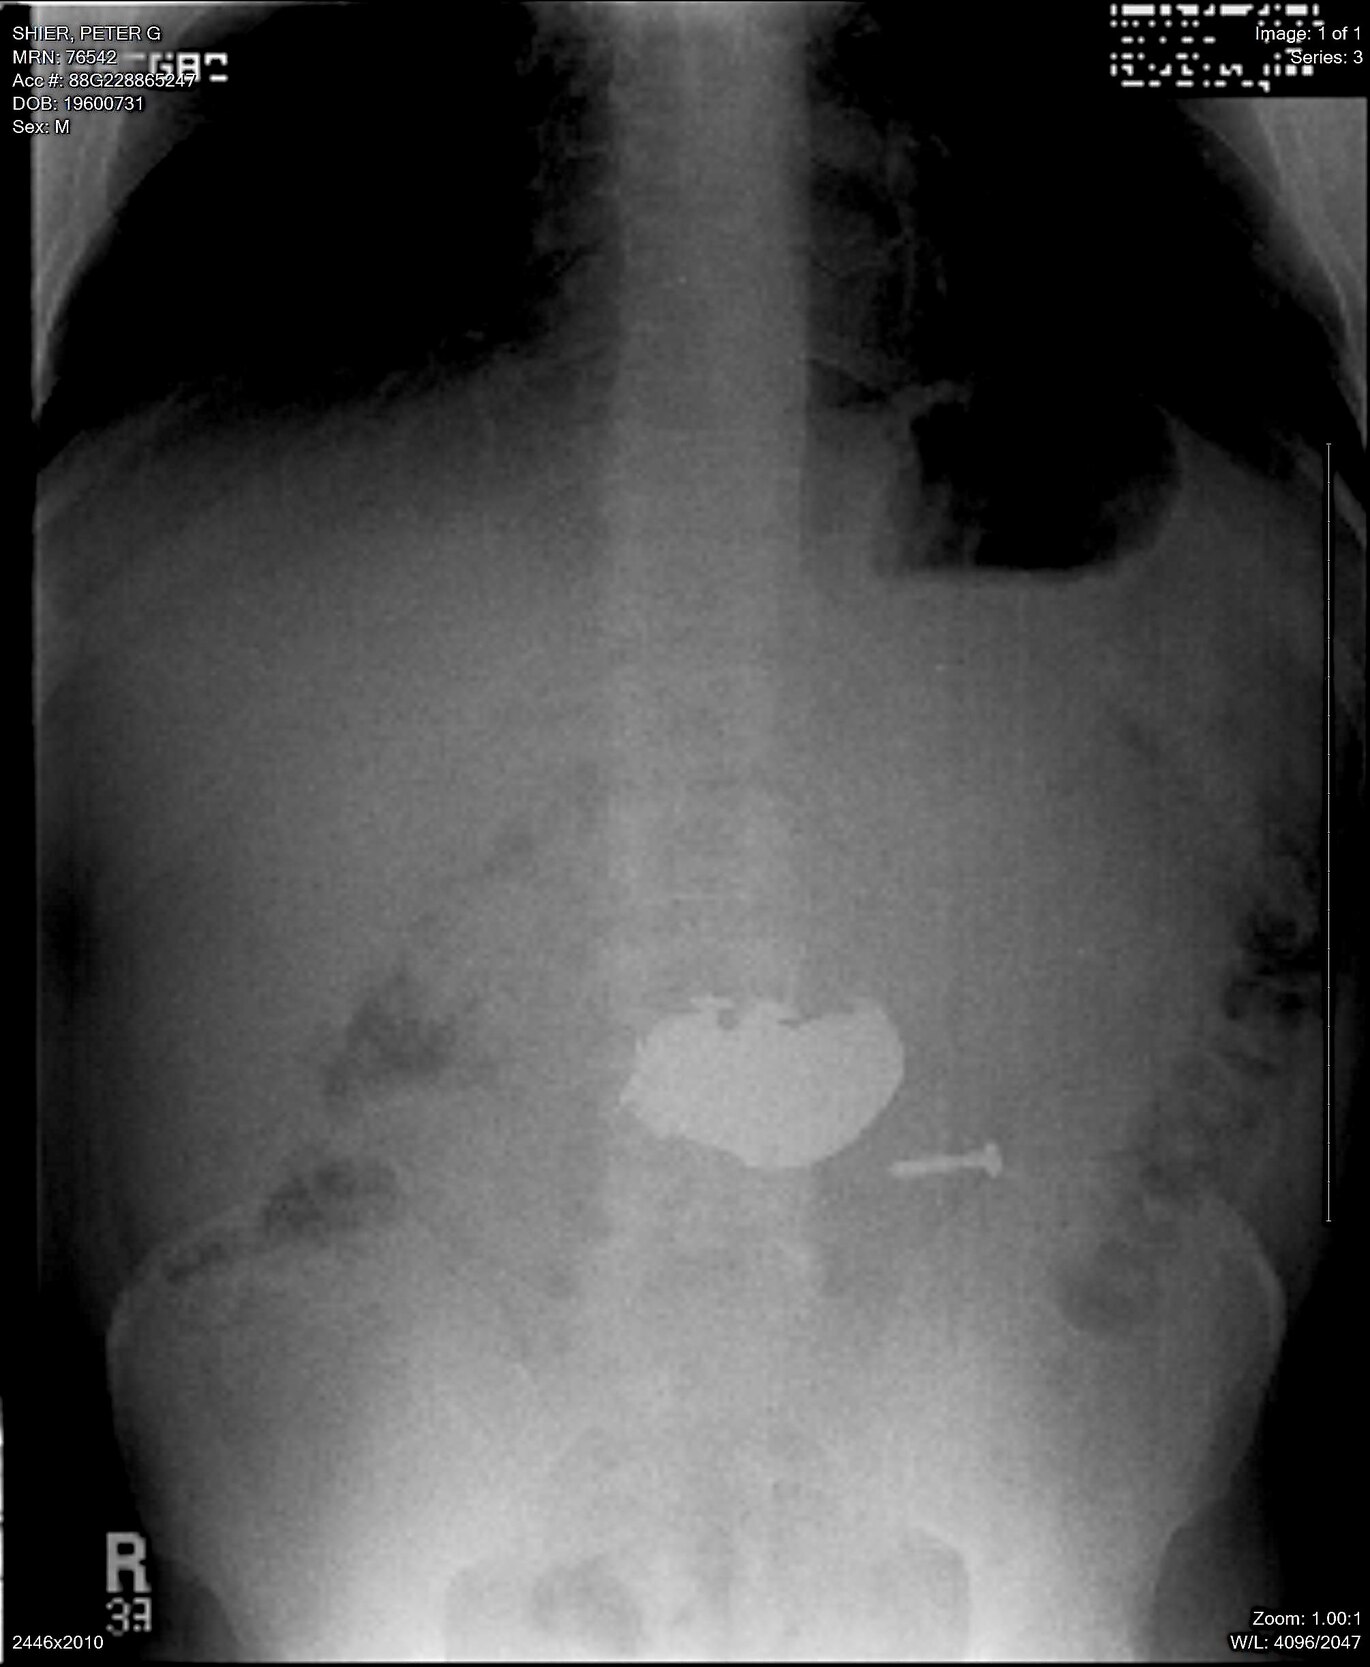

A 51 yo male psychiatric patient suffering depression and alcohol abuse presented to our emergency department on two separate occasions after ingestion of large amounts of foreign materials. Figure 1 demonstrates an abdominal x-ray on one of his admissions. Presentation, physical exam and x-ray findings were almost identical on both admissions, as were the types of materials ingested. The large number of objects made endoscopic extraction impractical and, since the many sharps that were swallowed included nails and screws, surgical removal was required due to fear of perforation.

A defibrillator magnet (commonly found at the anesthesia station) was placed into a sterile specimen bag that was then inserted into a gastrotomy incision. The bag was tied at its opening to ensure sterility. As the magnet was inserted and pulled from the gastrotomy, the ferrous-based sharps clung to it, facilitating easy and safe removal (Figure 2). After all of the sharps were removed, the many remaining swallowed pennies were then safely scooped out with a gloved surgical hand. The small intestine was completely examined in surgery and no objects were found to have passed out of the stomach. This also was confirmed by a plain abdominal X-ray done post-operatively. The gastronomy was closed in a standard fashion. The patient had an uneventful post-operative course and was discharged 5 days after surgery.